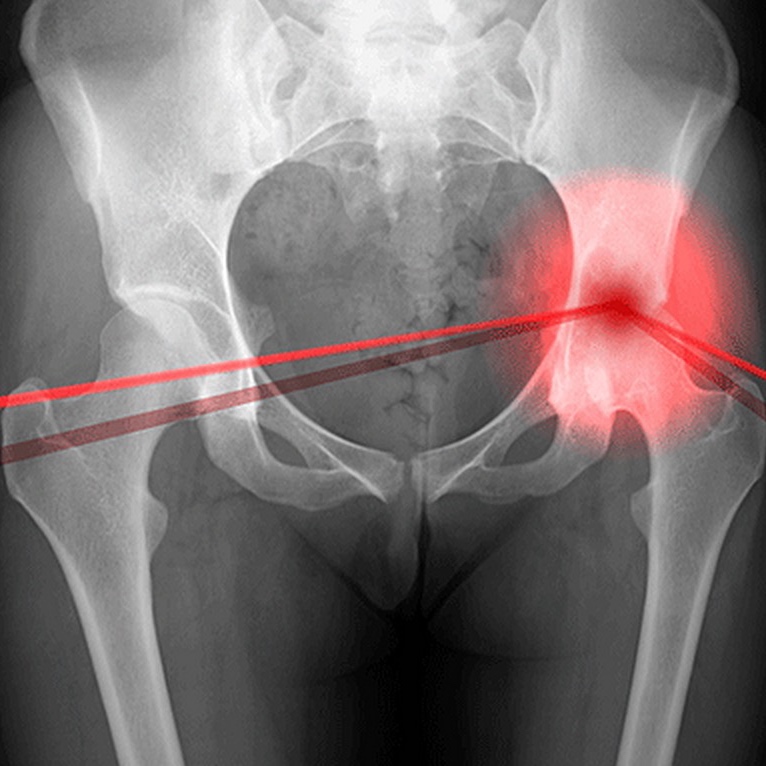

Фотографии и схемы: Коксит правого тазобедренного сустава